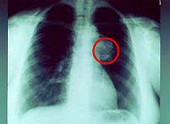

tiene cáncer (aquí un cáncer de pulmón)

y después de todo fue un médico con un diagnóstico que el papá tiene cáncer (aquí un cáncer de pulmón)

Todo el poder generado por su relación salió a la luz sólo en 1964. El médico le dijo a papá que tenía cáncer y calculó que, como máximo, le quedaban de seis meses a un año de vida.

Para los excelentes médicos y enfermeros del Centro Médico para Veteranos en Long Beach, él era un milagro ambulante. Lo controlaban con afecto y no podían entender cómo un cuerpo tan minado por el cáncer podía seguir funcionando tan bien.

-- foto radiográfica de cáncer de pulmón: http://www.krebsgesellschaft.de/pat_ka_lungenkrebs_diagnose.html?markierung=bronchial